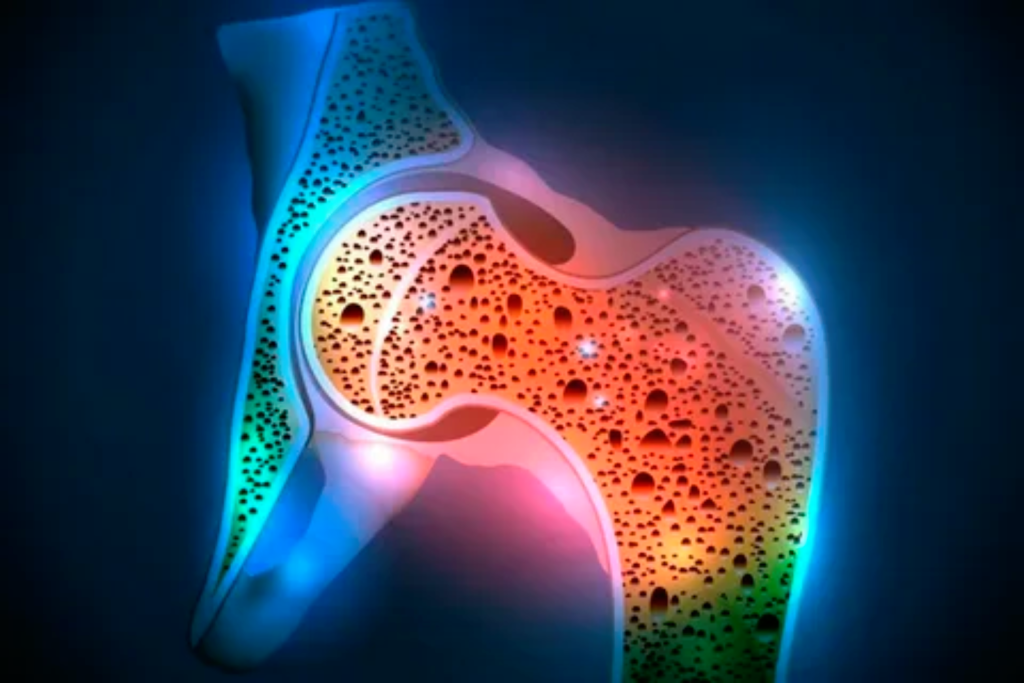

Osteoporosis

Vitamin D deficiency